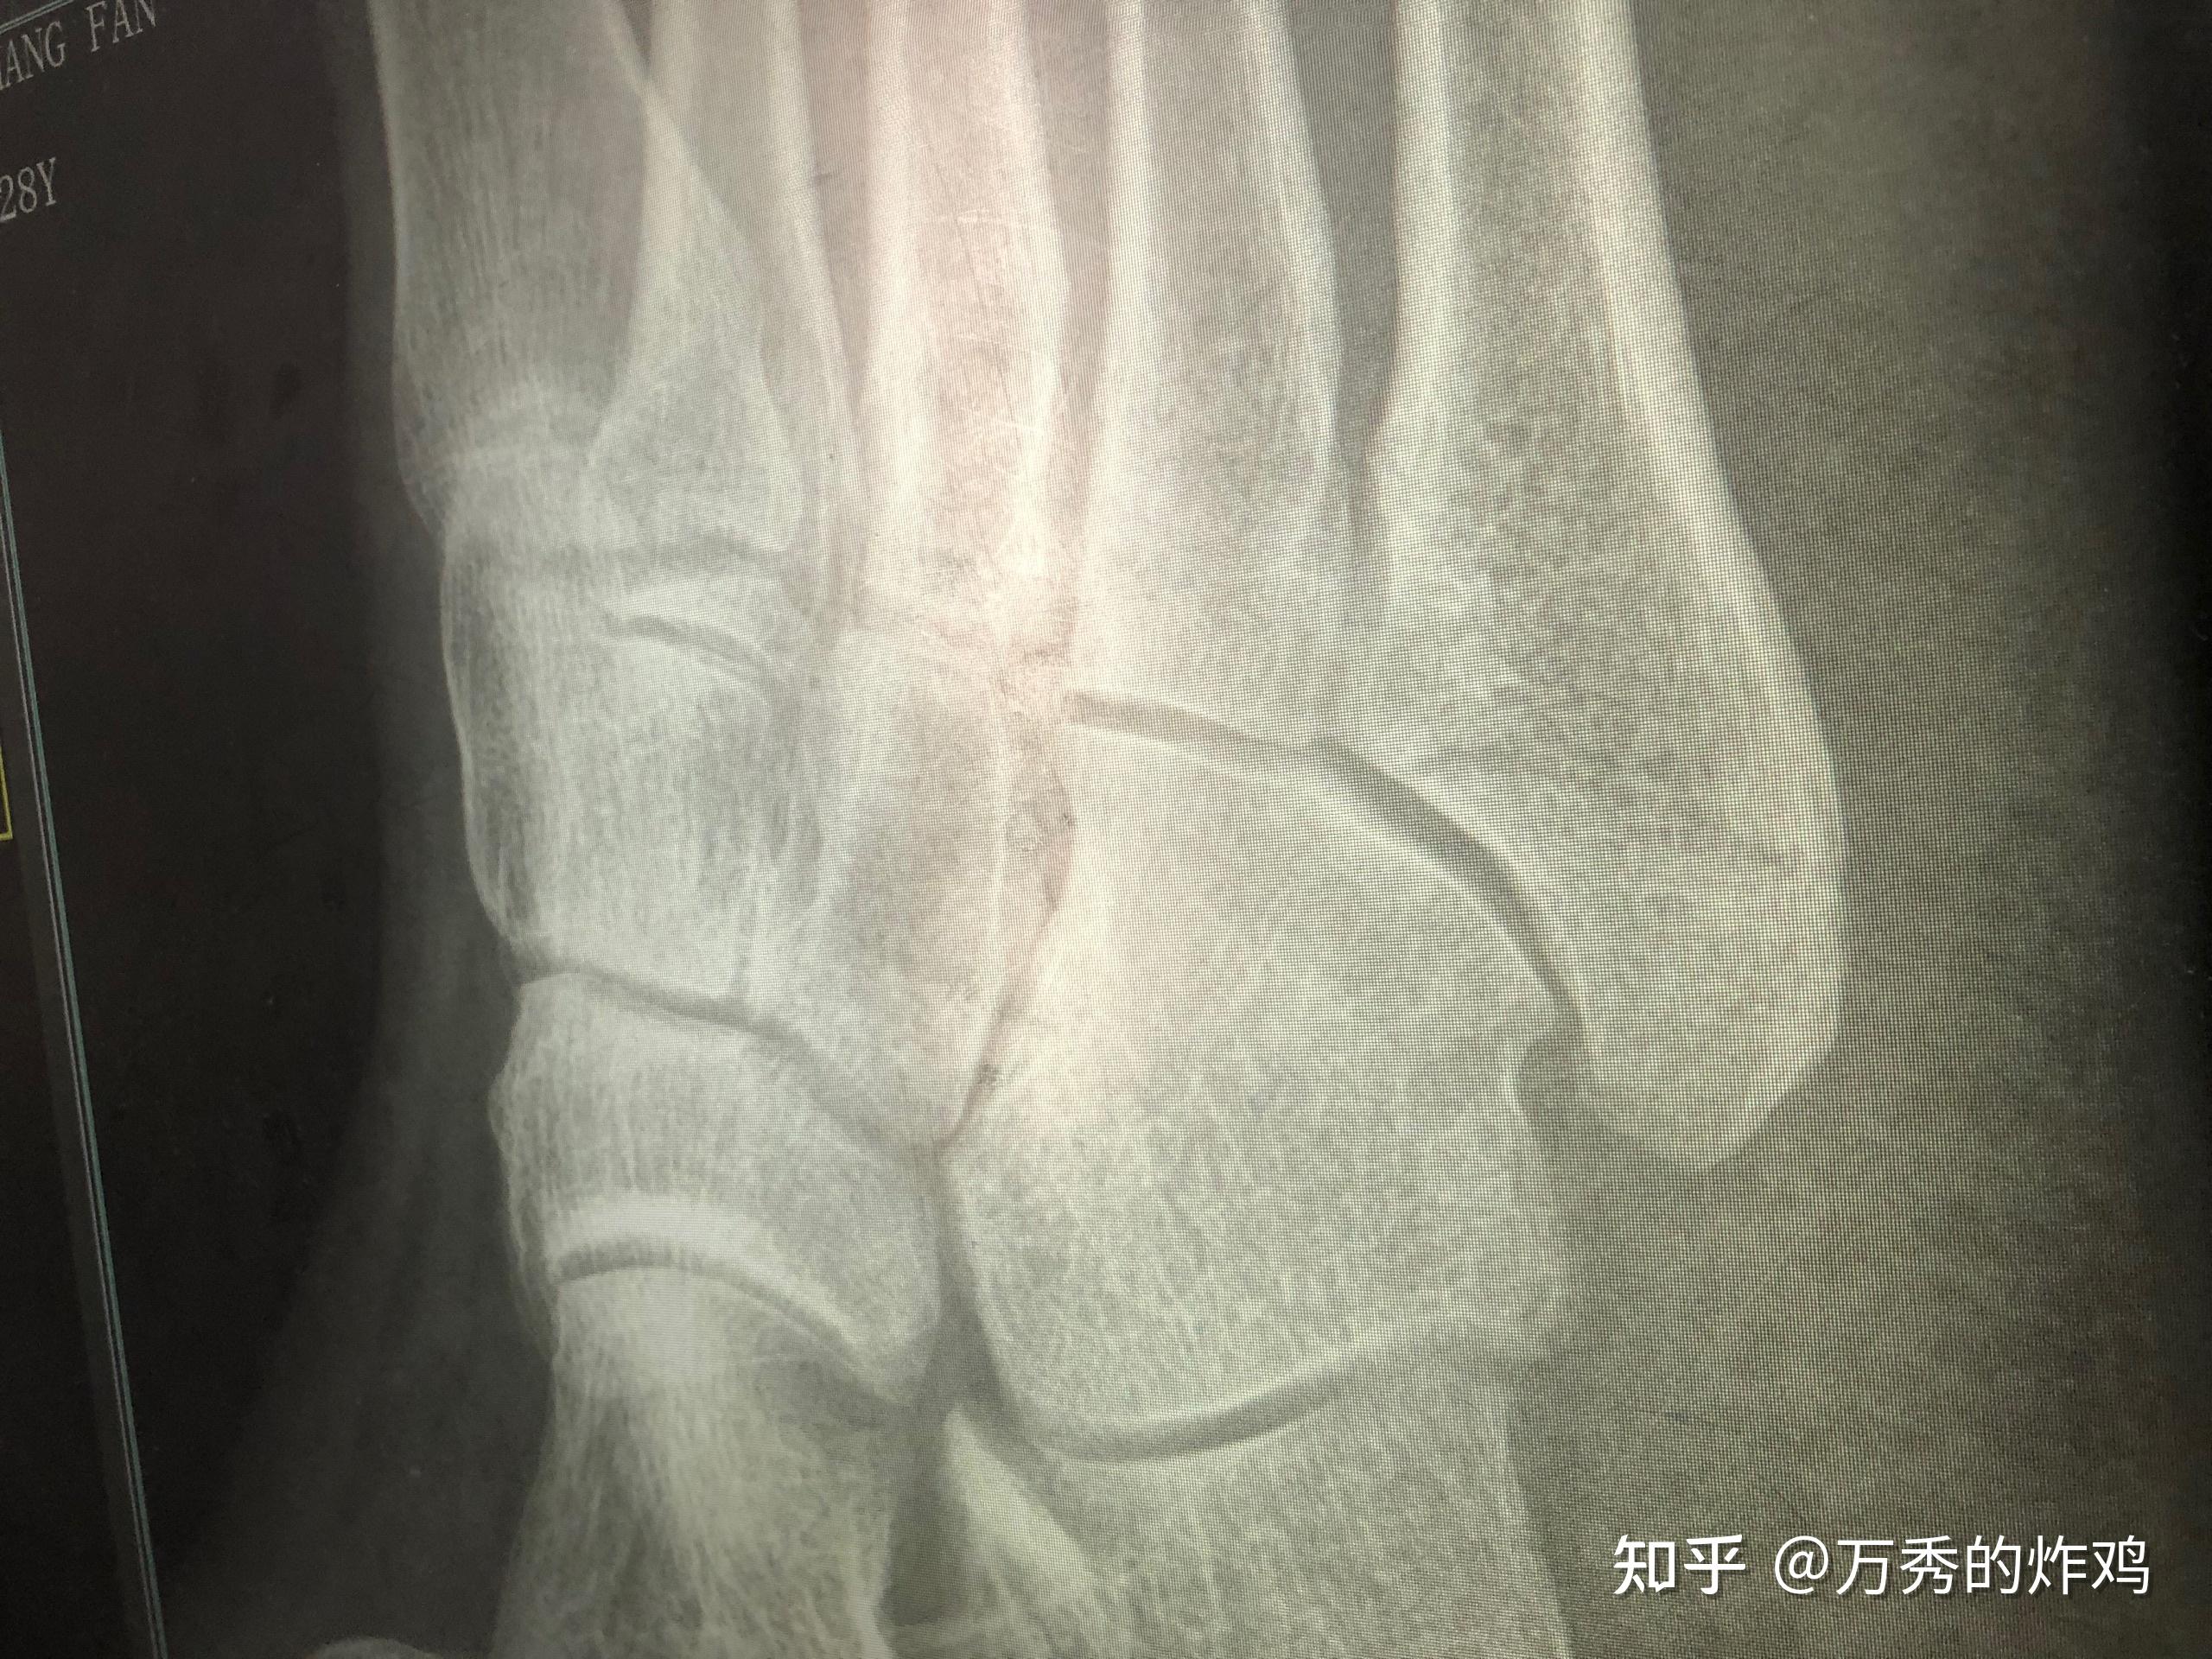

左足第五跖骨基底部骨折

第5跖骨基底部骨折

第五跖骨基底部骨折2020